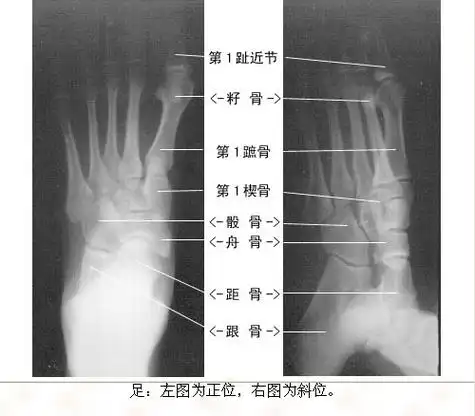

学习《x线读片指南》骨,关节系统——足